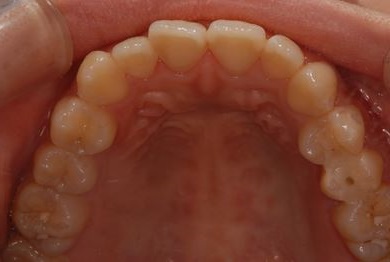

治療前

• 治療前